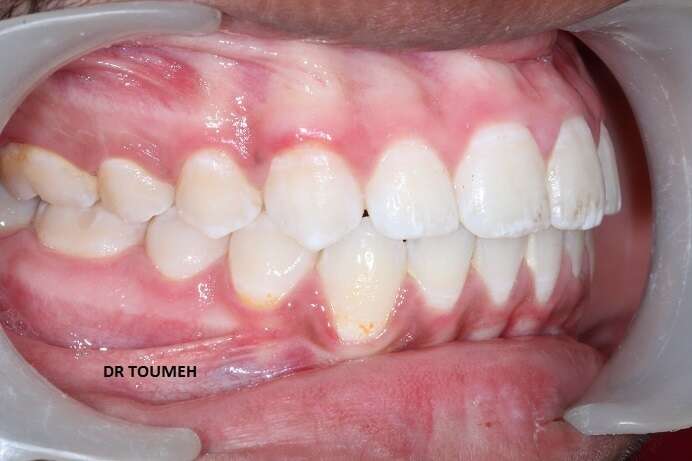

Le traitement Orthodontique doit commencer au bon moment le plutôt possible,

Avant

Votre Orthodontiste détermine le moment où il faut entamer le traitement orthodontique selon plusieurs paramétres (l'age de l'enfant, l'age osseux, le cas et le plan de traitement .....).